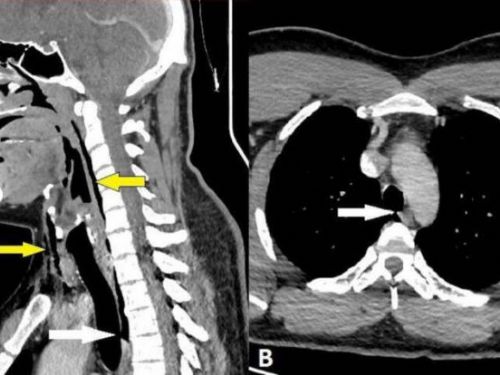

首見全球案例:用手捏住鼻子並閉住嘴,竟導致氣管撕裂

小心!強忍噴嚏有風險:全球首例捏鼻閉嘴導致氣管撕裂案例曝光。一名30多歲男子在開車時突然噴嚏,他試圖強忍不噴出聲音,結果 ...